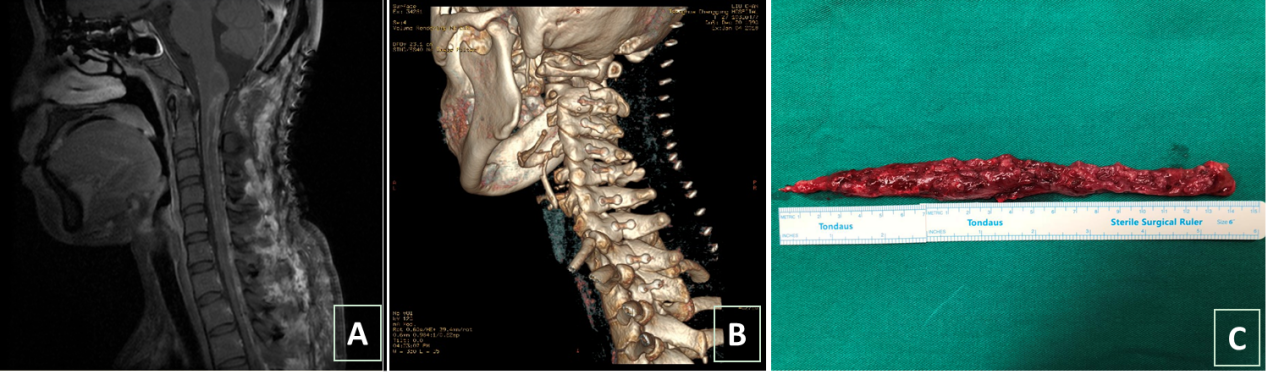

4个小时、6个小时、8个小时过去了,手术终于进行到了最重要的时刻:切除最后延髓的部分肿瘤。由于紧靠循环中枢,患者心率开始在50-100次/分波动,麻醉医生迅速调整药物,稳住患者心率、血压。最终肿瘤完整地切了下来,长21厘米。21:30小甜手术成功结束,整个过程历时14个小时,她的母亲握着王贵怀的双手,双眼噙着泪花,不停地说着感谢的话。

图2 术后影像  图A示:肿瘤完整切除,图B示:椎板完整复位,图C示:肿瘤标本

小甜目前精神状态良好,饮食睡眠基本正常,术后半月可独自坐起,并在家人搀扶下下地活动。